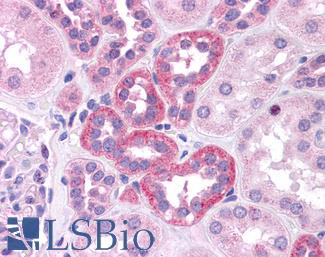

ERBB2 / HER2

Anti-ERBB2 / HER2 antibody IHC of human breast, carcinoma. Immunohistochemistry of formalin-fixed, paraffin-embedded tissue after heat-induced antigen retrieval. Antibody LS-B2133 concentration 5 ug/ml.